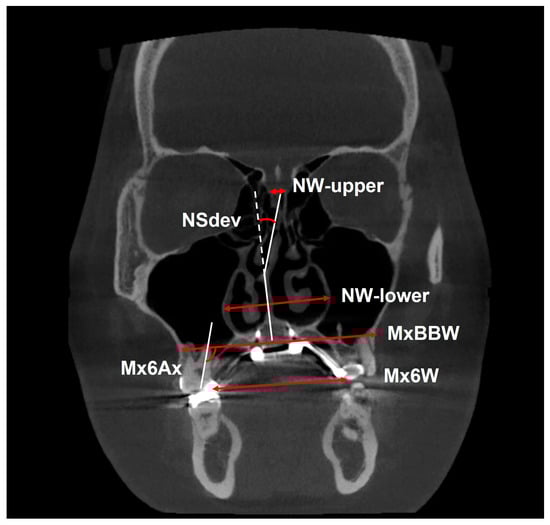

| NSdev (Figure 5) | Nasal septum deviation; the angle between the top and bottom of the nasal septum (°). | Measurements are taken from a slice of the root apex of the palatal side of the left maxillary first molar in the coronal plane. |

| NW-lower (Figure 5) | Lower nasal width; width of the lower nasal cavity, length of the line connecting the maximum convexity of the left and right nasal cavities (mm). | |

| NW-upper (Figure 5) | Upper nasal width; length of the line connecting the uppermost points of the left and right nasal cavities (mm). | |

| MxBBW (Figure 5) | Maxillary basal bone width; distance from the line connecting the roots of the left and right maxillary first molars to the tangent of the outer surface of the cortical bone of the left and right basal bones (mm). | |

| Mx6W (Figure 5) | Maxillary intermolar width; length of the line connecting the palatal cusps of the left and right maxillary first molars (mm). | |

| Mx6Ax (Figure 5) | Maxillary first molar axis; the medial angle (°) between the line extending the long axis of the palatal root of the maxillary first molar and the MxBBW (°). | |

| NSdev (°) ** | 142.93 ± 54.46 | 141.42 ± 54.47 | 1.51 ± 4.94 | 0.15 | 0.40 | 0.40 | |

| NW-lower (mm) * | 31.62 ± 2.83 | 34.56 ± 3.26 | 2.95 ± 1.16 | <0.001 *** | 0.40 | 0.40 | |

| NW-upper (mm) * | 4.2 ± 1.35 | 4.73 ± 1.39 | 0.52 ± 0.33 | <0.001 *** | 0.40 | 0.40 | |

| MxBBW (mm) * | 62.98 ± 3.50 | 66.54 ± 3.85 | 3.56 ± 1.18 | <0.001 *** | 0.40 | 0.40 | |

| Mx6W (mm) ** | 40.01 ± 2.98 | 45.46 ± 3.57 | 5.44 ± 1.77 | <0.001 *** | 0.40 | 0.40 | |

| Mx6Ax (°) * | 97.47 ± 7.16 | 100.48 ± 7.17 | 3.01 ± 2.56 | <0.001 *** | 0.40 | 0.40 |